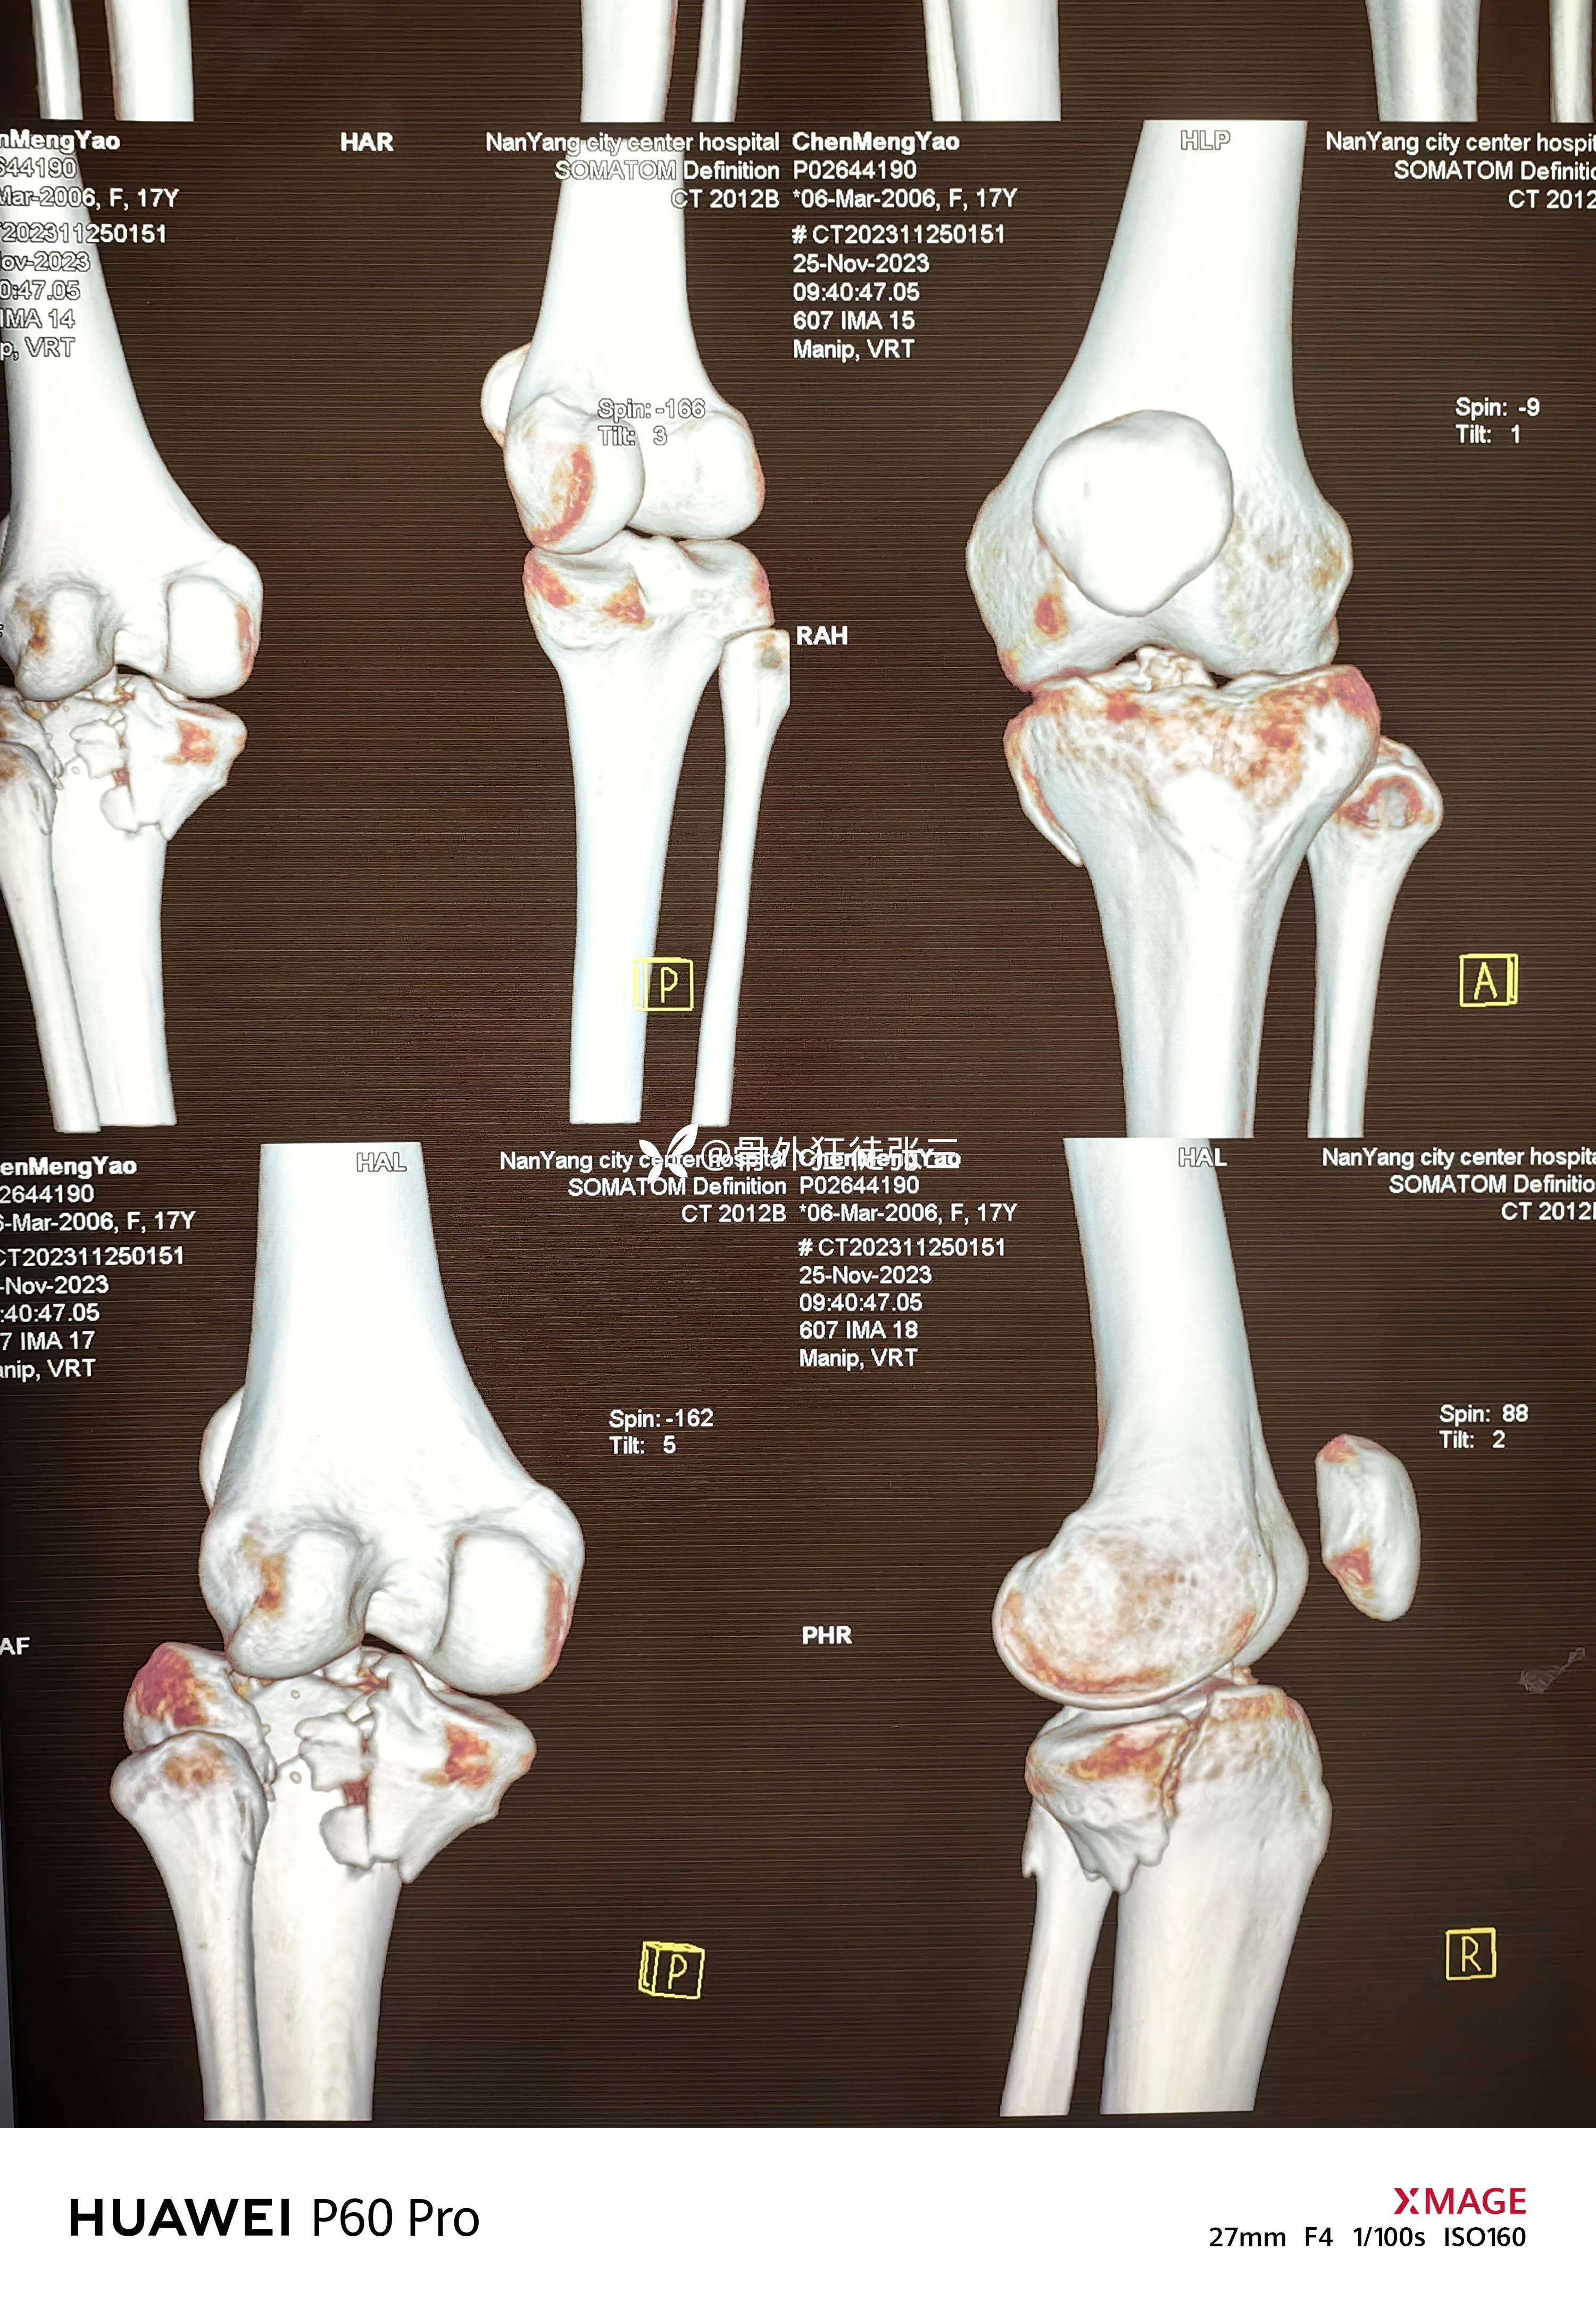

胫骨平台骨折术后,腓总神经损伤,

主诉:右胫骨平台骨折术后膝、踝关节活动和感觉障碍3月余。

2023.12.08,在当地医院行胫骨平台骨折手术

辅助检查:

第一次手术后复查